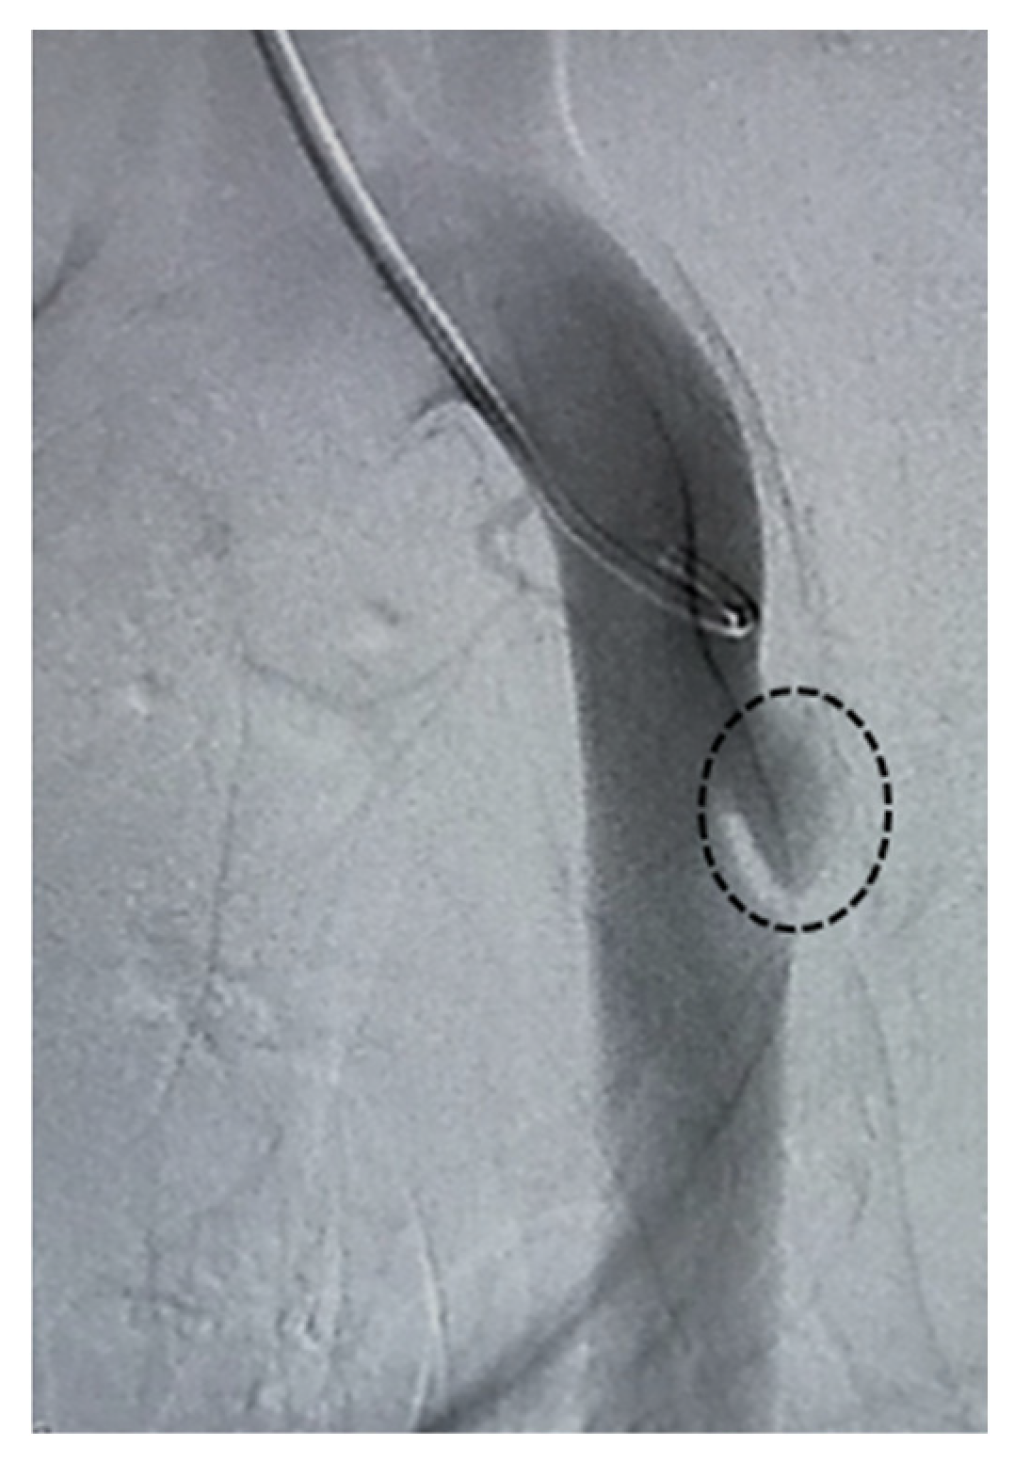

3.3. Transplantation

The angiographic catheter prepositioned within the aneurysm model (Figure 6A) was maintained in situ during and after SG deployment (Figure 6B), creating a condition that minimized intraluminal blood washout within the aneurysm sac. Under these conditions, the HMSC fiber was transplanted through the catheter and into the aneurysm sac. Although the HMSC fiber itself was not directly visualized by angiography, no residual fibers were observed within the catheter lumen, and the catheter was removed smoothly without resistance. Furthermore, follow-up angiography performed using a pigtail catheter demonstrated sustained aneurysm sealing after the procedure (Figure 6C). Collectively, these observations are consistent with the successful intraluminal delivery of the HMSC fiber into the aneurysm sac.

Angiographic imaging of the aneurysm model with a catheter prepositioned within the aneurysm sac (demarcated by the dashed line) (A). SG deployment covering the aneurysm while maintaining the catheter position within the aneurysm sac, enabling the administration of the HMSC fibers under reduced blood washout conditions (B). Follow-up angiography using a pigtail catheter after the procedure, confirming sustained aneurysm sealing (C).